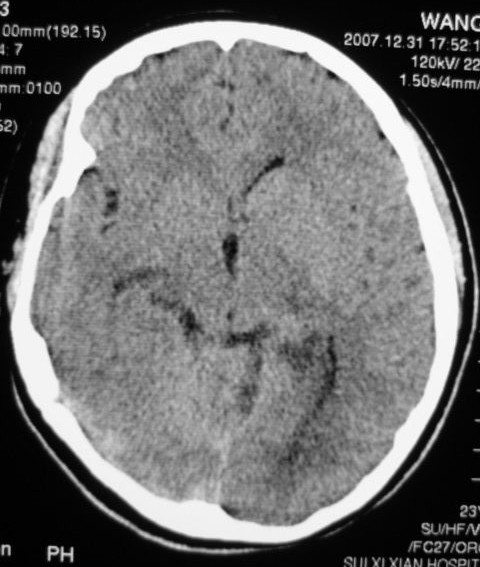

以下是引用zjzjr在2008-2-19 15:45:00的发言:[br]左侧小脑缺血性脑梗塞,基底节区脑梗塞,强烈建议血管造影,除外烟雾病。

以下是引用玉真在2008-2-19 17:46:00的发言:[br]多发性脑梗塞,不知病人是否有风心或先心病史